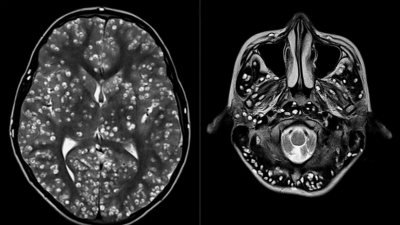

Tras practicarle una resonancia magnética y exámenes de ultrasonido, los especialistas encontraron que la corteza cerebral y el tronco encefálico del paciente estaban llenos de larvas.